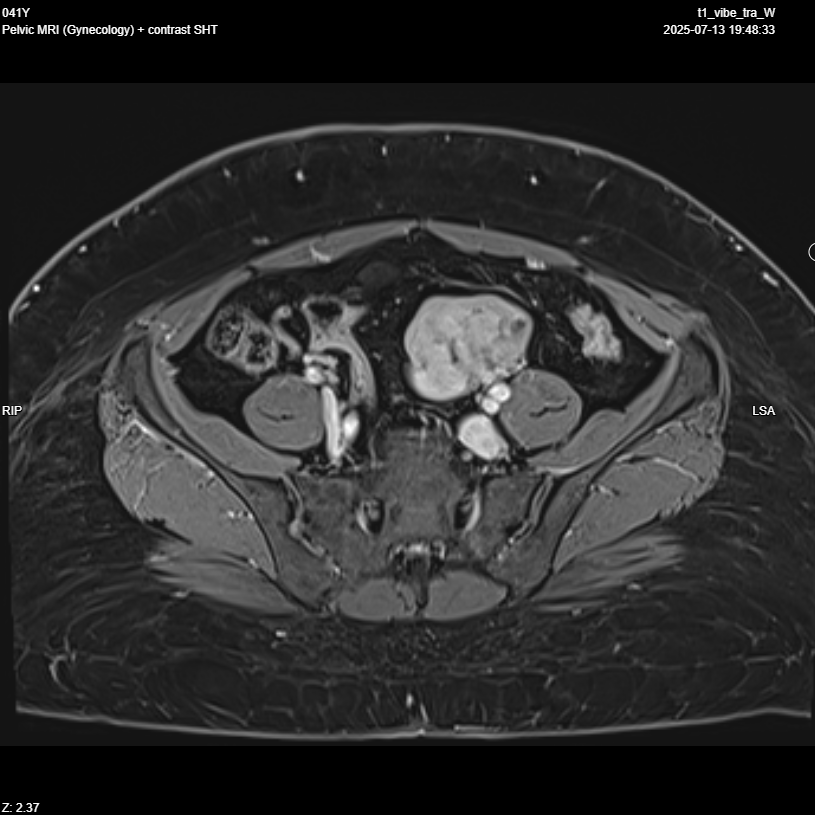

Pelvic MRI with IV contrast

· Evidence of left adnexal irregular lobulated shape solid mass replacing most of left ovarian parenchyma , T1 iso intense , T2 hypo intense , restricted in DWI, no fat , no calcification , after giving contrast showing diffuse progressive hyper enhancement , with high risk curve of enhancement , these radiological features highly suspicious for malignant ovarian tumor, O-RADS 5.